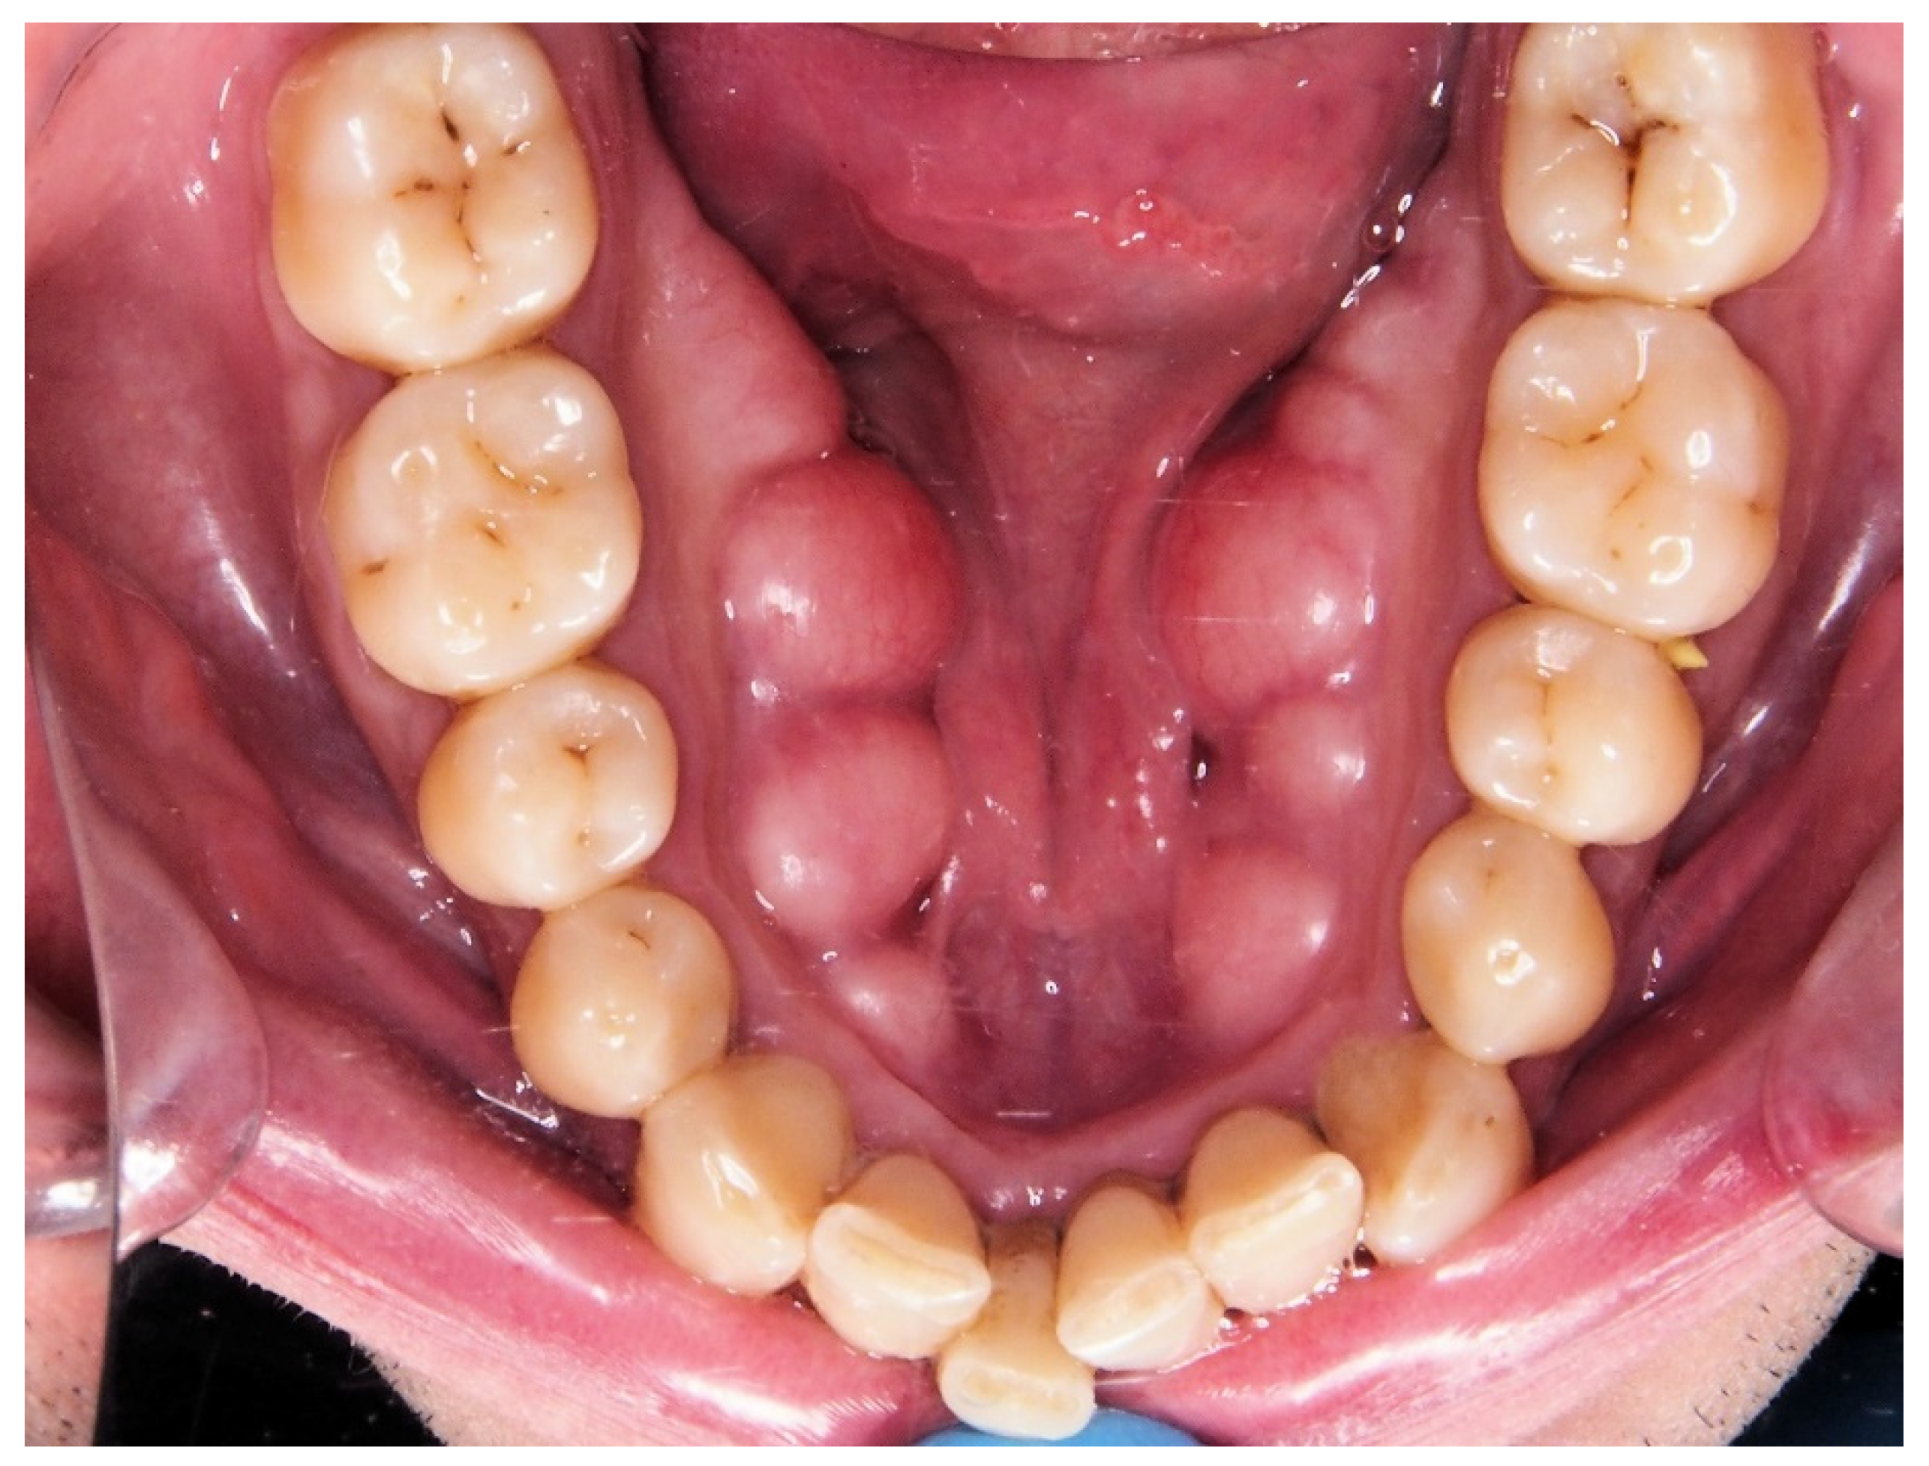

| Torus. Nº (%) | 34 (33%) | ||